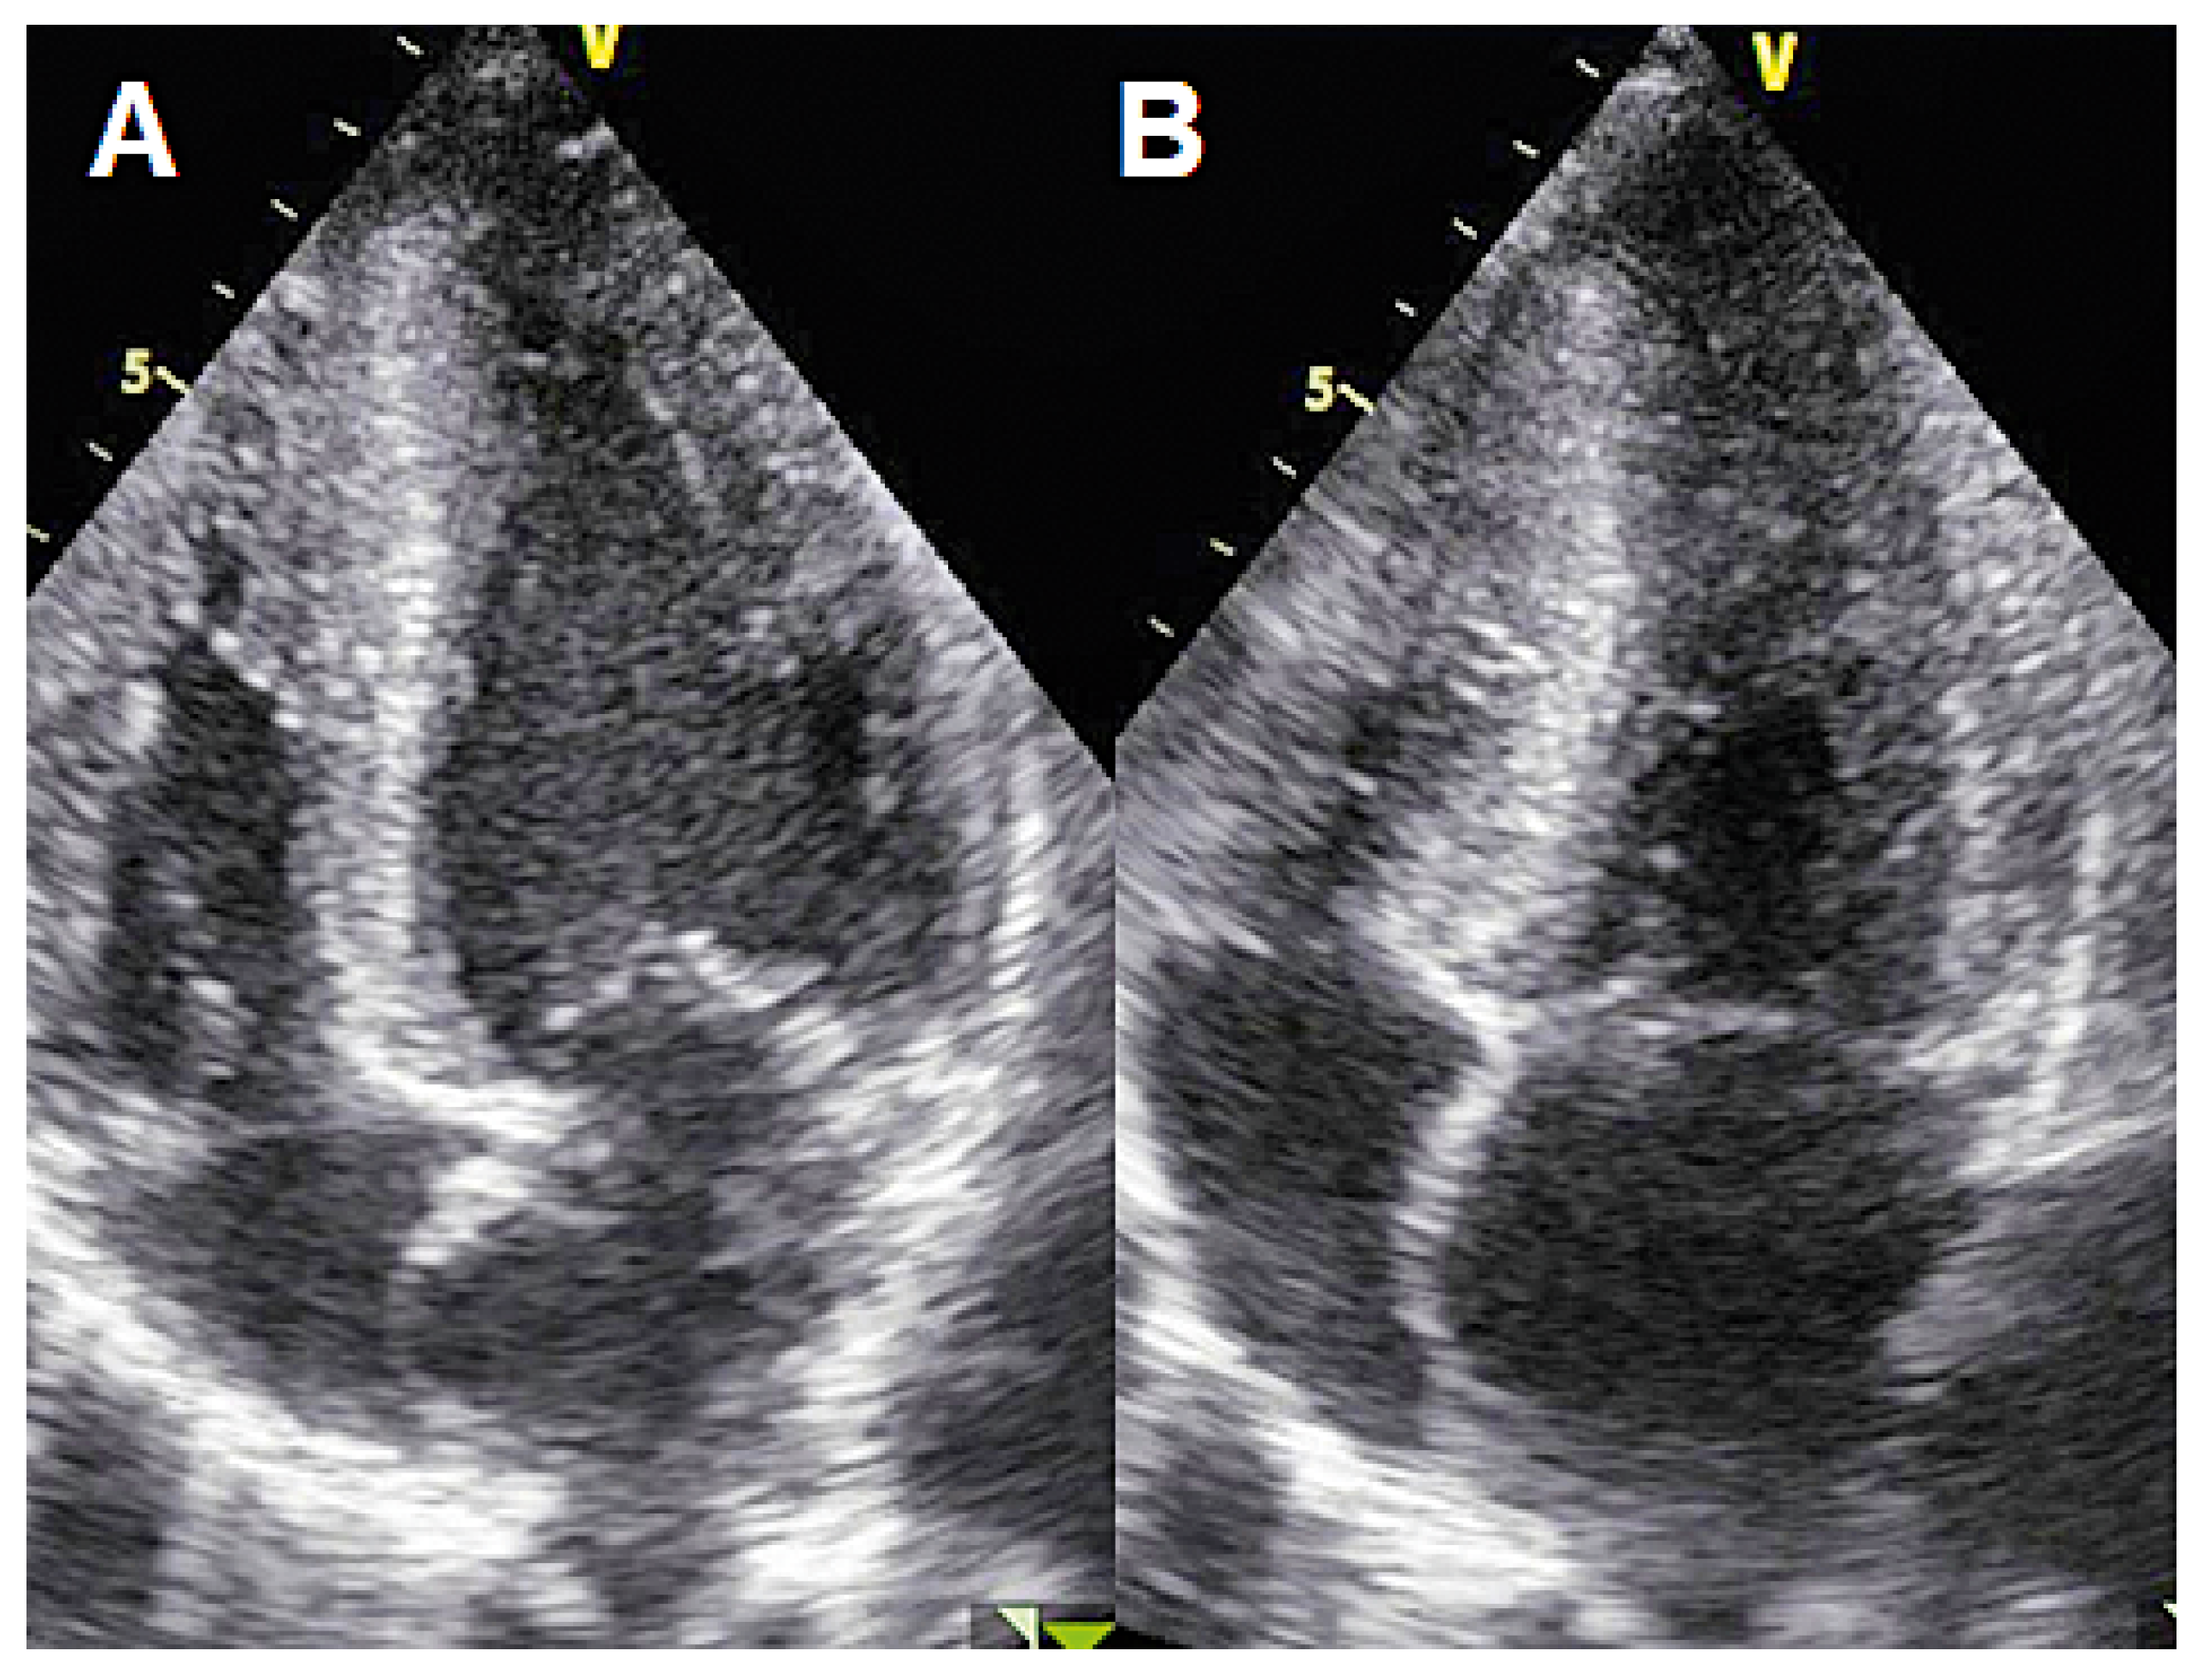

Case 1

Case 2